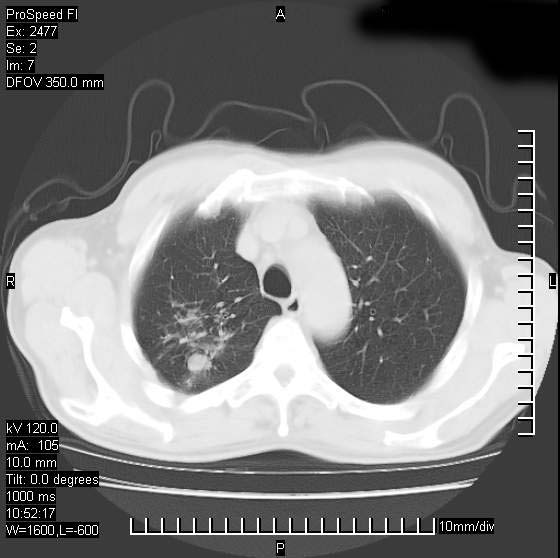

以下是引用天南地北在2007-10-9 14:29:00的发言:[br]1:右上肺结核[br]2:右肺下叶肿块:不支持肺癌,首先考虑炎性病变-肺脓疡可能性大[br]理由:1:临床病史支持,肺脓肿症状不明显应该是不规则服药造成。[br] 2:肿块边缘模糊,周围可见炎性渗出,长毛刺,内见支气管征,不过有点不规则。[br] 我感觉下肺癌这个诊断有点偏左,建议积极抗炎治疗后复查

以下是引用卜一在2007-10-9 15:55:00的发言:[br][br] [br] 1:右上肺结核[br]2:右肺下叶肿块:不支持肺癌,首先考虑炎性病变-肺脓疡可能性大[br]理由:1:临床病史支持,肺脓肿症状不明显应该是不规则服药造成。[br] 2:肿块边缘模糊,周围可见炎性渗出,长毛刺,内见空气支气管征,不过有点不规则。[br] 我感觉下肺癌这个诊断有点偏左,建议积极抗炎治疗后复查![br]支持! [br] [br] [br]

以下是引用wxy7406在2007-10-9 21:02:00的发言:[br]结合临床病史首先考虑感染性病变,但周围型肺癌不能除外,1.患者年龄偏大2.临床有咯血3.(也觉得是最重要的一点)病灶内有偏心性空洞。

以下是引用王仕学在2007-10-9 13:48:00的发言:[br]右下肺周围性肺癌可能性大,最好活检吧

以下是引用hhcckk在2007-10-9 15:18:00的发言:[br]右上肺病灶考虑结核,病灶多种形态并存(纤维化、增殖性病灶并存)[br]右下肺病灶比较难说,个人意见更趋向于“天南地北”的诊断----肺脓肿[br]1、病人有明显的寒战,高热,肿瘤病人很少出现[br]2、病灶周围的肺纹理走向柔和,没有肿瘤病灶常见的集束征[br]3、病灶边缘的毛刺较长,恶性肿瘤多为短毛刺[br]痰中血丝和病人的年龄是两个不利于良性肿块的因素,建议早点活检

以下是引用ydx_74在2007-10-9 15:53:00的发言:[br]右上肺结核,右下中心性肺癌可能大,肺门淋巴结肿大。